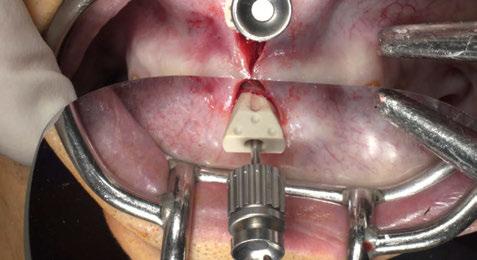

uando se trata de diseñar una prótesis de arcada completa sobre implantes y con carga inmediata es necesario transmitir al laboratorio dental toda la información para poder realizar un diseño correcto de la prótesis provisional inmediata. Se trata de obtener el mejor resultado desde el punto de vista estético y funcional con esa primera prótesis provisional fija. Por eso se ha creado la técnica Di2gitalArch®, en la que el elemento i2 servirá como estructura de referencia fija que facilite la alineación y superposición de los archivos virtuales obtenidos, mediante escáner intraoral, en diferentes situaciones clínicas de un mismo paciente.

Diseñado fundamentalmente para procedimientos de carga inmediata con un escáner intraoral, y con la finalidad de copiar o recrear la situación previa o inicial del mismo, el sistema permite la superposición de todos los archivos que contengan el elemento i2 en la misma posición espacial y obtener un

flujo de trabajo nuevo, tanto a nivel clínico como en el proceso de diseño CAD/CAM, más rápido, fácil y preciso, tanto a nivel funcional como estético.

El cirujano puede optar por dos variantes del Sistema Di2gitalArch®:

Sistema 1.0 y Sistema 2.0. La principal diferencia entre ambos es que el Sistema 1.0 es un sistema ideado para situaciones no quirúrgicas (Figuras 1-44).

SISTEMA 1.0

Está compuesto por un tornillo autorroscante de fijación de 2 mm de diámetro y de 10,5 o 12,5 mm de longitud, que se usa para fijar el scanbody Di 2 gitalArch® al maxilar del paciente y un scanbody diseñado específicamente para esta aplicación, en cuanto a sus dimensiones y morfología. Otros diseños de scanbody no han resultado plenamente efectivos ya que se trata de alinear todo un maxilar.

La unión al maxilar del paciente, aunque muy estable, no es absolutamente rígida, estable y puede ser movido ligeramente de posición con los separadores o cualquier maniobra durante la cirugía.

Por ello está indicado, al finalizar el tratamiento del paciente, durante el escaneado intraoral para copiar la información de la prótesis provisional fija y poder realizar la prótesis definitiva, especialmente en el maxilar inferior. El empleo del tornillo de Di2gitalArch® 1 está indicado en la toma de impresión digital para: